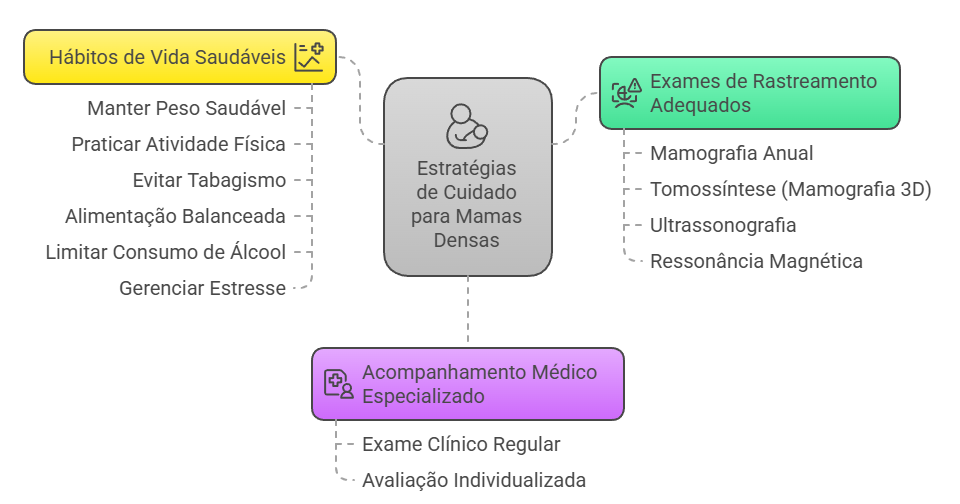

Exames de Rastreamento Adequados

- Manter a Mamografia Anual: Ela continua sendo o exame padrão-ouro para o rastreamento do câncer de mama. Mesmo com o desafio da densidade, a mamografia ainda é capaz de detectar microcalcificações suspeitas, que podem ser o primeiro sinal de um câncer.

- Considerar a Tomossíntese (Mamografia 3D): Esta tecnologia mais moderna é uma excelente opção para mamas densas. A tomossíntese realiza múltiplas “fatias” finas da mama, diminuindo a sobreposição de tecidos e reduzindo o efeito de mascaramento. Isso aumenta a taxa de detecção de câncer e diminui a necessidade de reconvocar a paciente para imagens adicionais.

- Complementar com Ultrassonografia: Em muitos casos, especialmente para mulheres com mamas densas e risco intermediário, eu recomendo a ultrassonografia mamária como um exame complementar à mamografia. O ultrassom utiliza ondas sonoras e é excelente para visualizar nódulos que podem estar ocultos no tecido denso.

- Ressonância Magnética em Casos Específicos: Para mulheres com mamas densas e alto risco para câncer de mama (devido a histórico familiar forte, mutações genéticas como BRCA1/2, etc.), a ressonância magnética pode ser indicada como um exame de rastreamento adicional, por sua altíssima sensibilidade.

Acompanhamento Médico Especializado

- Exame clínico regular: Consultas periódicas com mastologista ajudam a detectar alterações físicas que podem não aparecer nos exames de imagem

- Avaliação individualizada: Cada caso deve ser analisado considerando idade, histórico familiar e outros fatores de risco

Hábitos de Vida Saudáveis

Não podemos esquecer dos fatores que ajudam a reduzir o risco geral de câncer de mama:

- Manter peso corporal saudável

- Praticar atividade física regularmente

- Evitar o tabagismo

- Seguir alimentação balanceada e nutritiva

- Limitar o consumo de álcool

- Gerenciar adequadamente o estresse